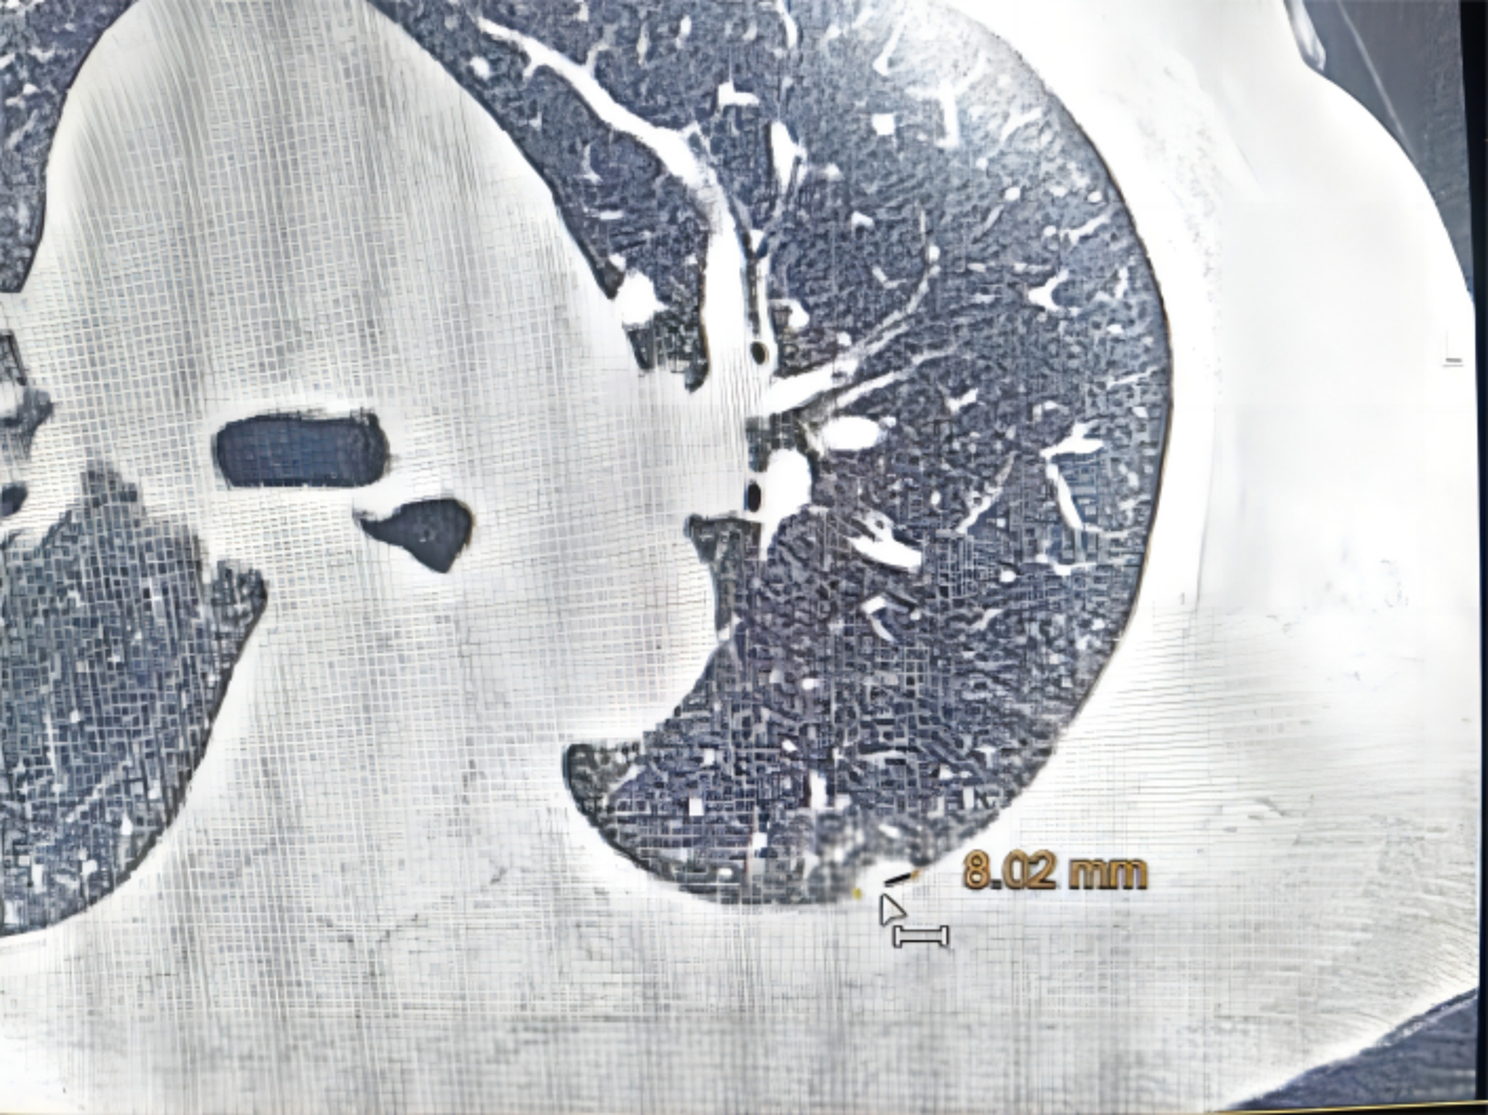

Pulmonary hamartomas are common. However, extrapulmonary hamartomas on the Visceral Pleura are very rare. We treated a patient with a pulmonary nodule at the left lower lobe by uniportal video-assisted thoracoscopic wedge resection, which showed a yellow nodule located on the visceral pleura. Pathology showed that the nodule contained a small amount of cartilage tissue and was diagnosed as hamartoma. Fat-coated extrapulmonary hamartomas located on the visceral pleura have not been previously documented in the literature. This article presents a case of such an extrapulmonary hamartoma.